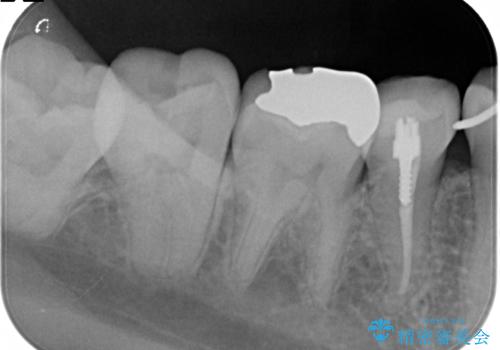

- 下顎の銀歯と、かぶせ物が外れたままになっている歯の治療を主訴に来院されました。

左下の奥歯はかぶせ物が外れて、土台が露出している状態でした。

セラミッククラウンにて下顎の左右の歯にセラミッククラウンを装着する計画としました。